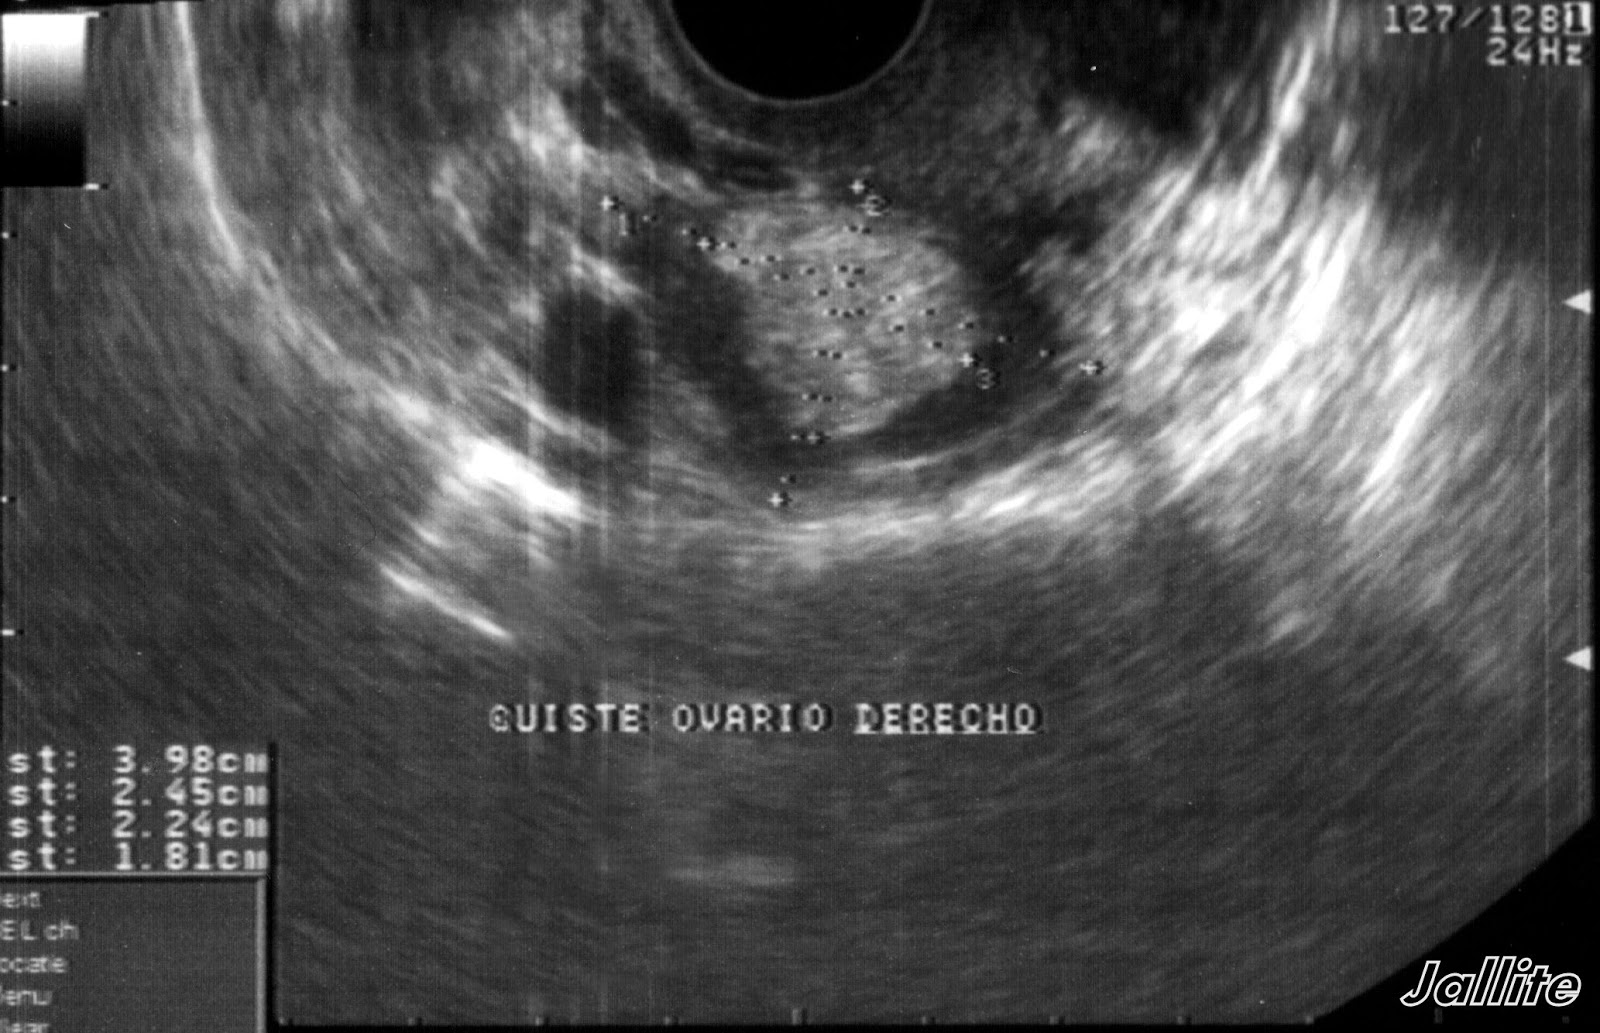

Diagnóstico imagenológico de un teratoma gigante de ovario

Teratoma ovarico ecografia 2D 3D Dr. Rafael Ortega Muñoz Ginecologo Ciud... Ecografia